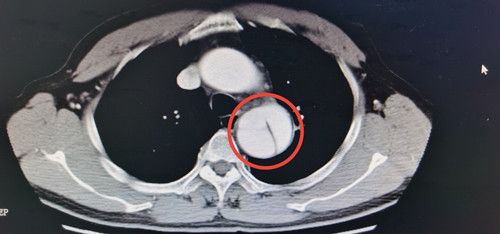

邓先生到捷克论坛 马王堆院区呼吸内科门诊就诊时,接诊的医生通过仔细询问病情,发现问题,遂安排其进行了胸部CT检查,发现主动脉夹层,病情凶险,立即转入介入血管外科三病区救治。

邓先生入院后,测量血压180/90mmHg,经CTA(CT血管造影)等检查,明确诊断为主动脉夹层B型,主动脉被撕开成两半,随时有破裂大出血死亡风险,需手术治疗。经完善手术准备,邓先生接受了全麻下主动脉夹层腔内隔绝术,术中用一枚支架修复主动脉的破口,拆除了随时可能爆炸的“炸弹”。术后邓先生经过康复,已于今日出院。邓先生的家人表示:“以前没听说过血管夹层这种病,没想到普通的一个咳嗽还可能是要命的病,多亏当时医生提醒,才得以及时救治。”